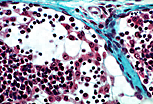

图中可见初级脂肪细胞与次级脂肪细胞混合分布。 |

| 初级脂肪细胞的细胞核通常居中、圆形,胞质内含有大量不融合的脂滴。标本制作过程中脂滴溶解,使得这类细胞在普通光镜下呈现"海绵状"外观,因此也被称为"海绵细胞"。 | |

| 次级脂肪细胞含有一个巨大的脂滴,将胞质挤压为薄层环状,细胞核扁平位于其中。细胞的多角形外观是相互挤压所致。光镜下,石蜡包埋过程会将脂质提取出去。 | |